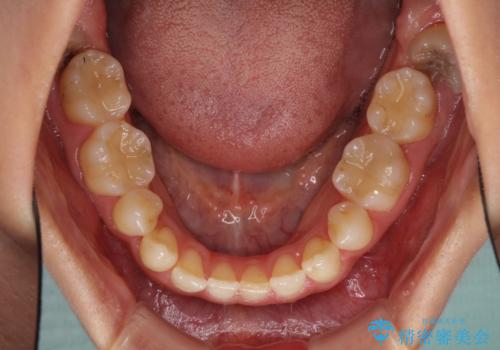

- 以前の矯正治療の後戻りにより、上の前歯にスペースができたことを気にして来院された患者様です。

インビザラインを用いて前歯のスペースを閉じつつ、上下の咬み合わせを構築していくこととしました。